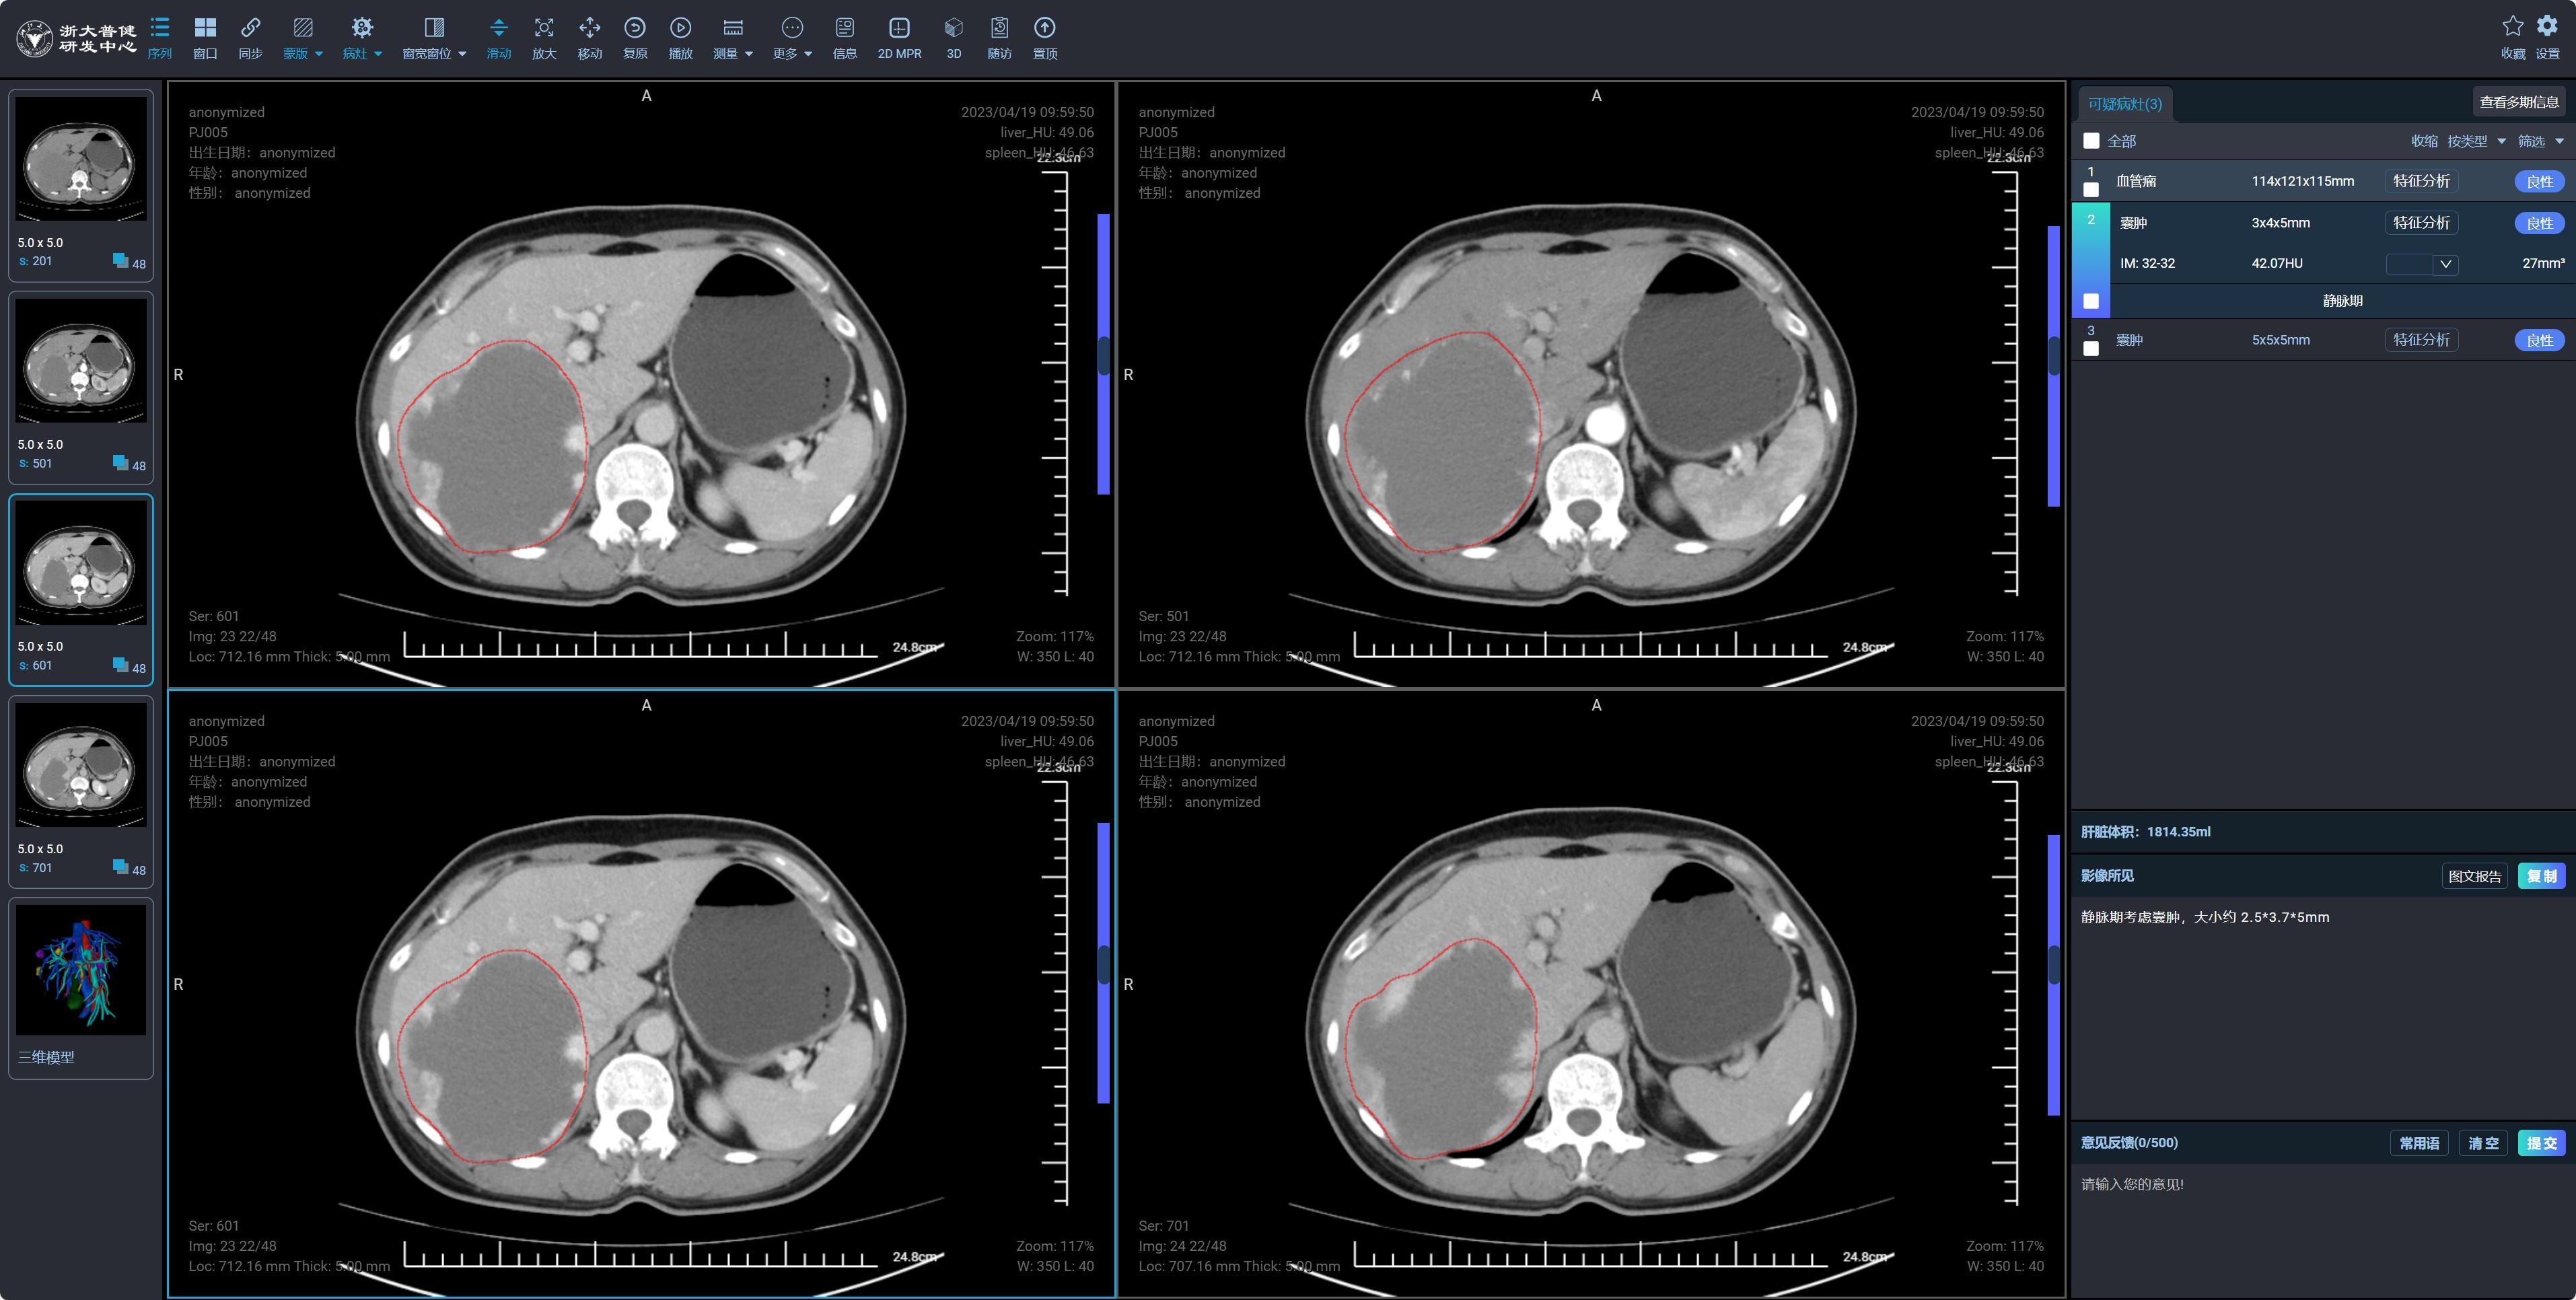

聚焦肝脏疾病早期智能诊断与 AI 临床辅助决策,构建基于 Transformer 结构的肝脏病灶分割模型,提取多期增强 CT 影像上下文信息;融合大语言模型与多模态生成式 AI 技术,打造具备图文联合理解与医学推理能力的多模态大模型体系,首创多智能体协作诊断机制,实现病灶分割 — 知识检索 — 诊断生成全流程闭环。

成功构建国内领先的肝脏病灶分割模型,病灶分割 Dice 系数达 81%,为目前国内最高水平,显著提升复杂病灶识别能力;开发的 AI 辅助检测平台获得国家三类医疗器械生产许可证(国内唯二),在技术先进性与合规性上具备突出优势。

AI 辅助检测平台已在数十家医疗机构部署应用,有效提升医生阅片效率并降低误诊率;实现基于医学知识和上下文语义的智能分割推理能力,建成由图像智能体、知识智能体和报告生成智能体组成的自动诊断报告系统,显著提升诊疗智能化水平。未来将持续优化模型泛化能力、可解释性与端侧部署效率,构建 “可信赖、可落地” 的新一代智能医疗核心技术平台。